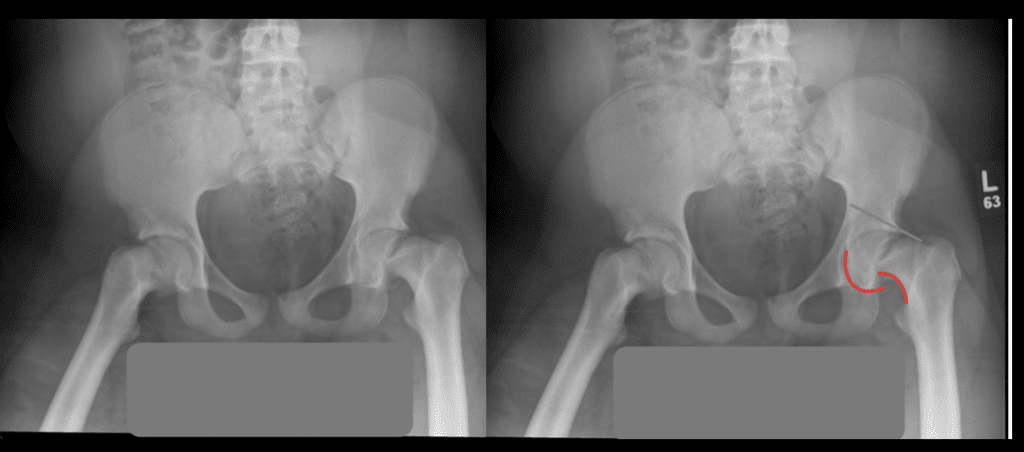

#Hip #Xray In A #child With Hip Pain Shows A Slipped Capital Femoral

epiphysis femoral slipped xray trauma

Slipped Capital Femoral Epiphysis Kleins Line

femoral epiphysis slipped capital scfe line klein head lateral medicoapps